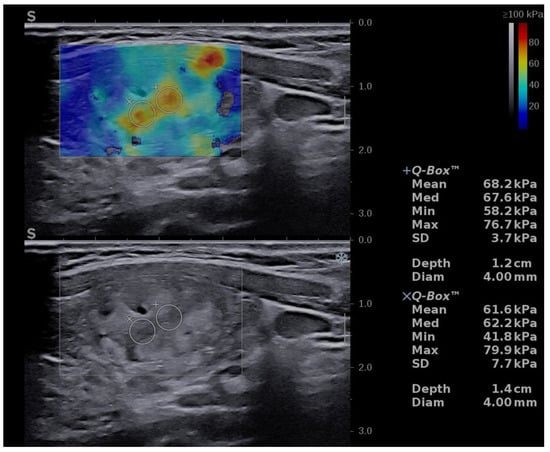

An upgrade of the risk category was made in eight cases with increased stiffness, defined as values of Mean EI > 30.5 kPa. Six cases were upgraded from low to intermediate risk and ten cases from intermediate to high risk (see Figure 4).

Figure 4.

Risk upgrade from intermediate risk in B-mode to high risk in B-mode + SWE due to increased stiffness (Mean EI = 68.2 kPa). Pathology report confirmed PTC.